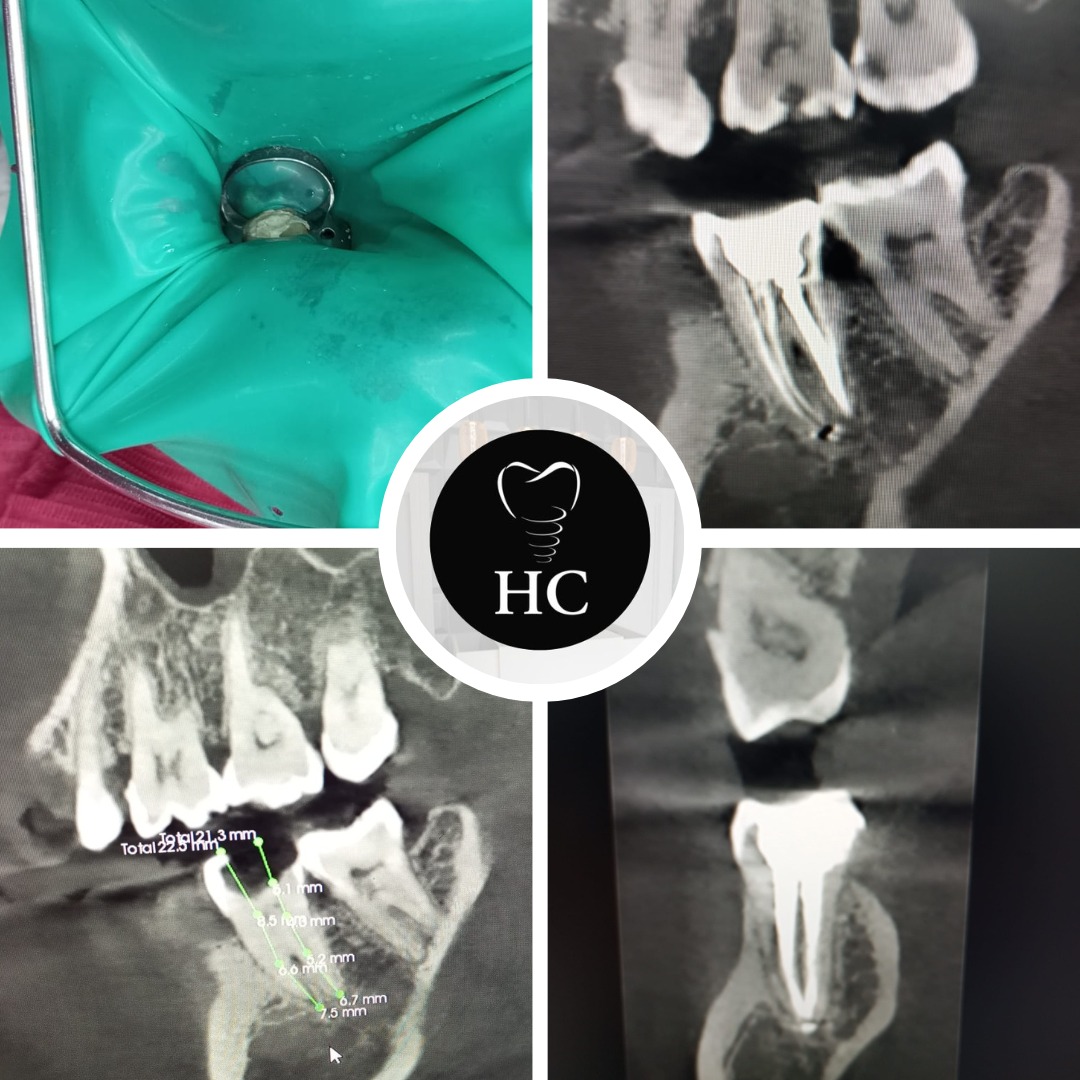

Galería

Algunos de nuestros tratamientos de endodoncia que permiten salvar piezas dentales, eliminar infecciones y devolver la salud y funcionalidad a tu sonrisa.